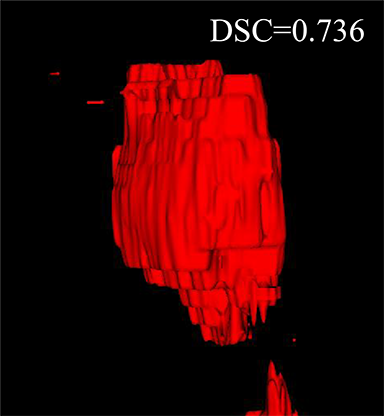

Comparison with related works. Table 1 reports the values of , and for different methods. Predicted masks of different methods are illustrated in Figure 9 and Figure 10, which respectively present results in 2D and 3D images. Through comprehensively analyzing these results, the proposed MMFNet actually have the following properties:

(i) It directly fuses 3D MRI images rather than 2D slices. Thus, it can effectively use meaningful information from neighboring slices of MRI to realize NPC segmentation. As shown in Table 2, MMFNet can bring , and improvements in and compared to the best method based on 2D images (Multi-modality patch-based CNN). And Figure 10 shows that 3D-based methods have less isolated regions (false positives) than 2D-based ones.